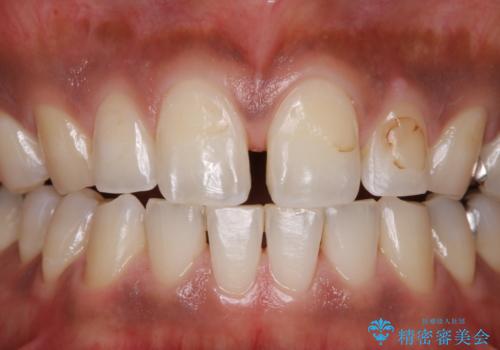

着色(ステイン)が裏表と付着し、全体的に歯石やプラーク(細菌の塊)も付着していたのでPMTC60分コース(自費クリーニング)を行いました。

クリーニングで、汚れを除去した際に、古い詰め物の色がより目立ってきたため、今後やり替えすることになりました。